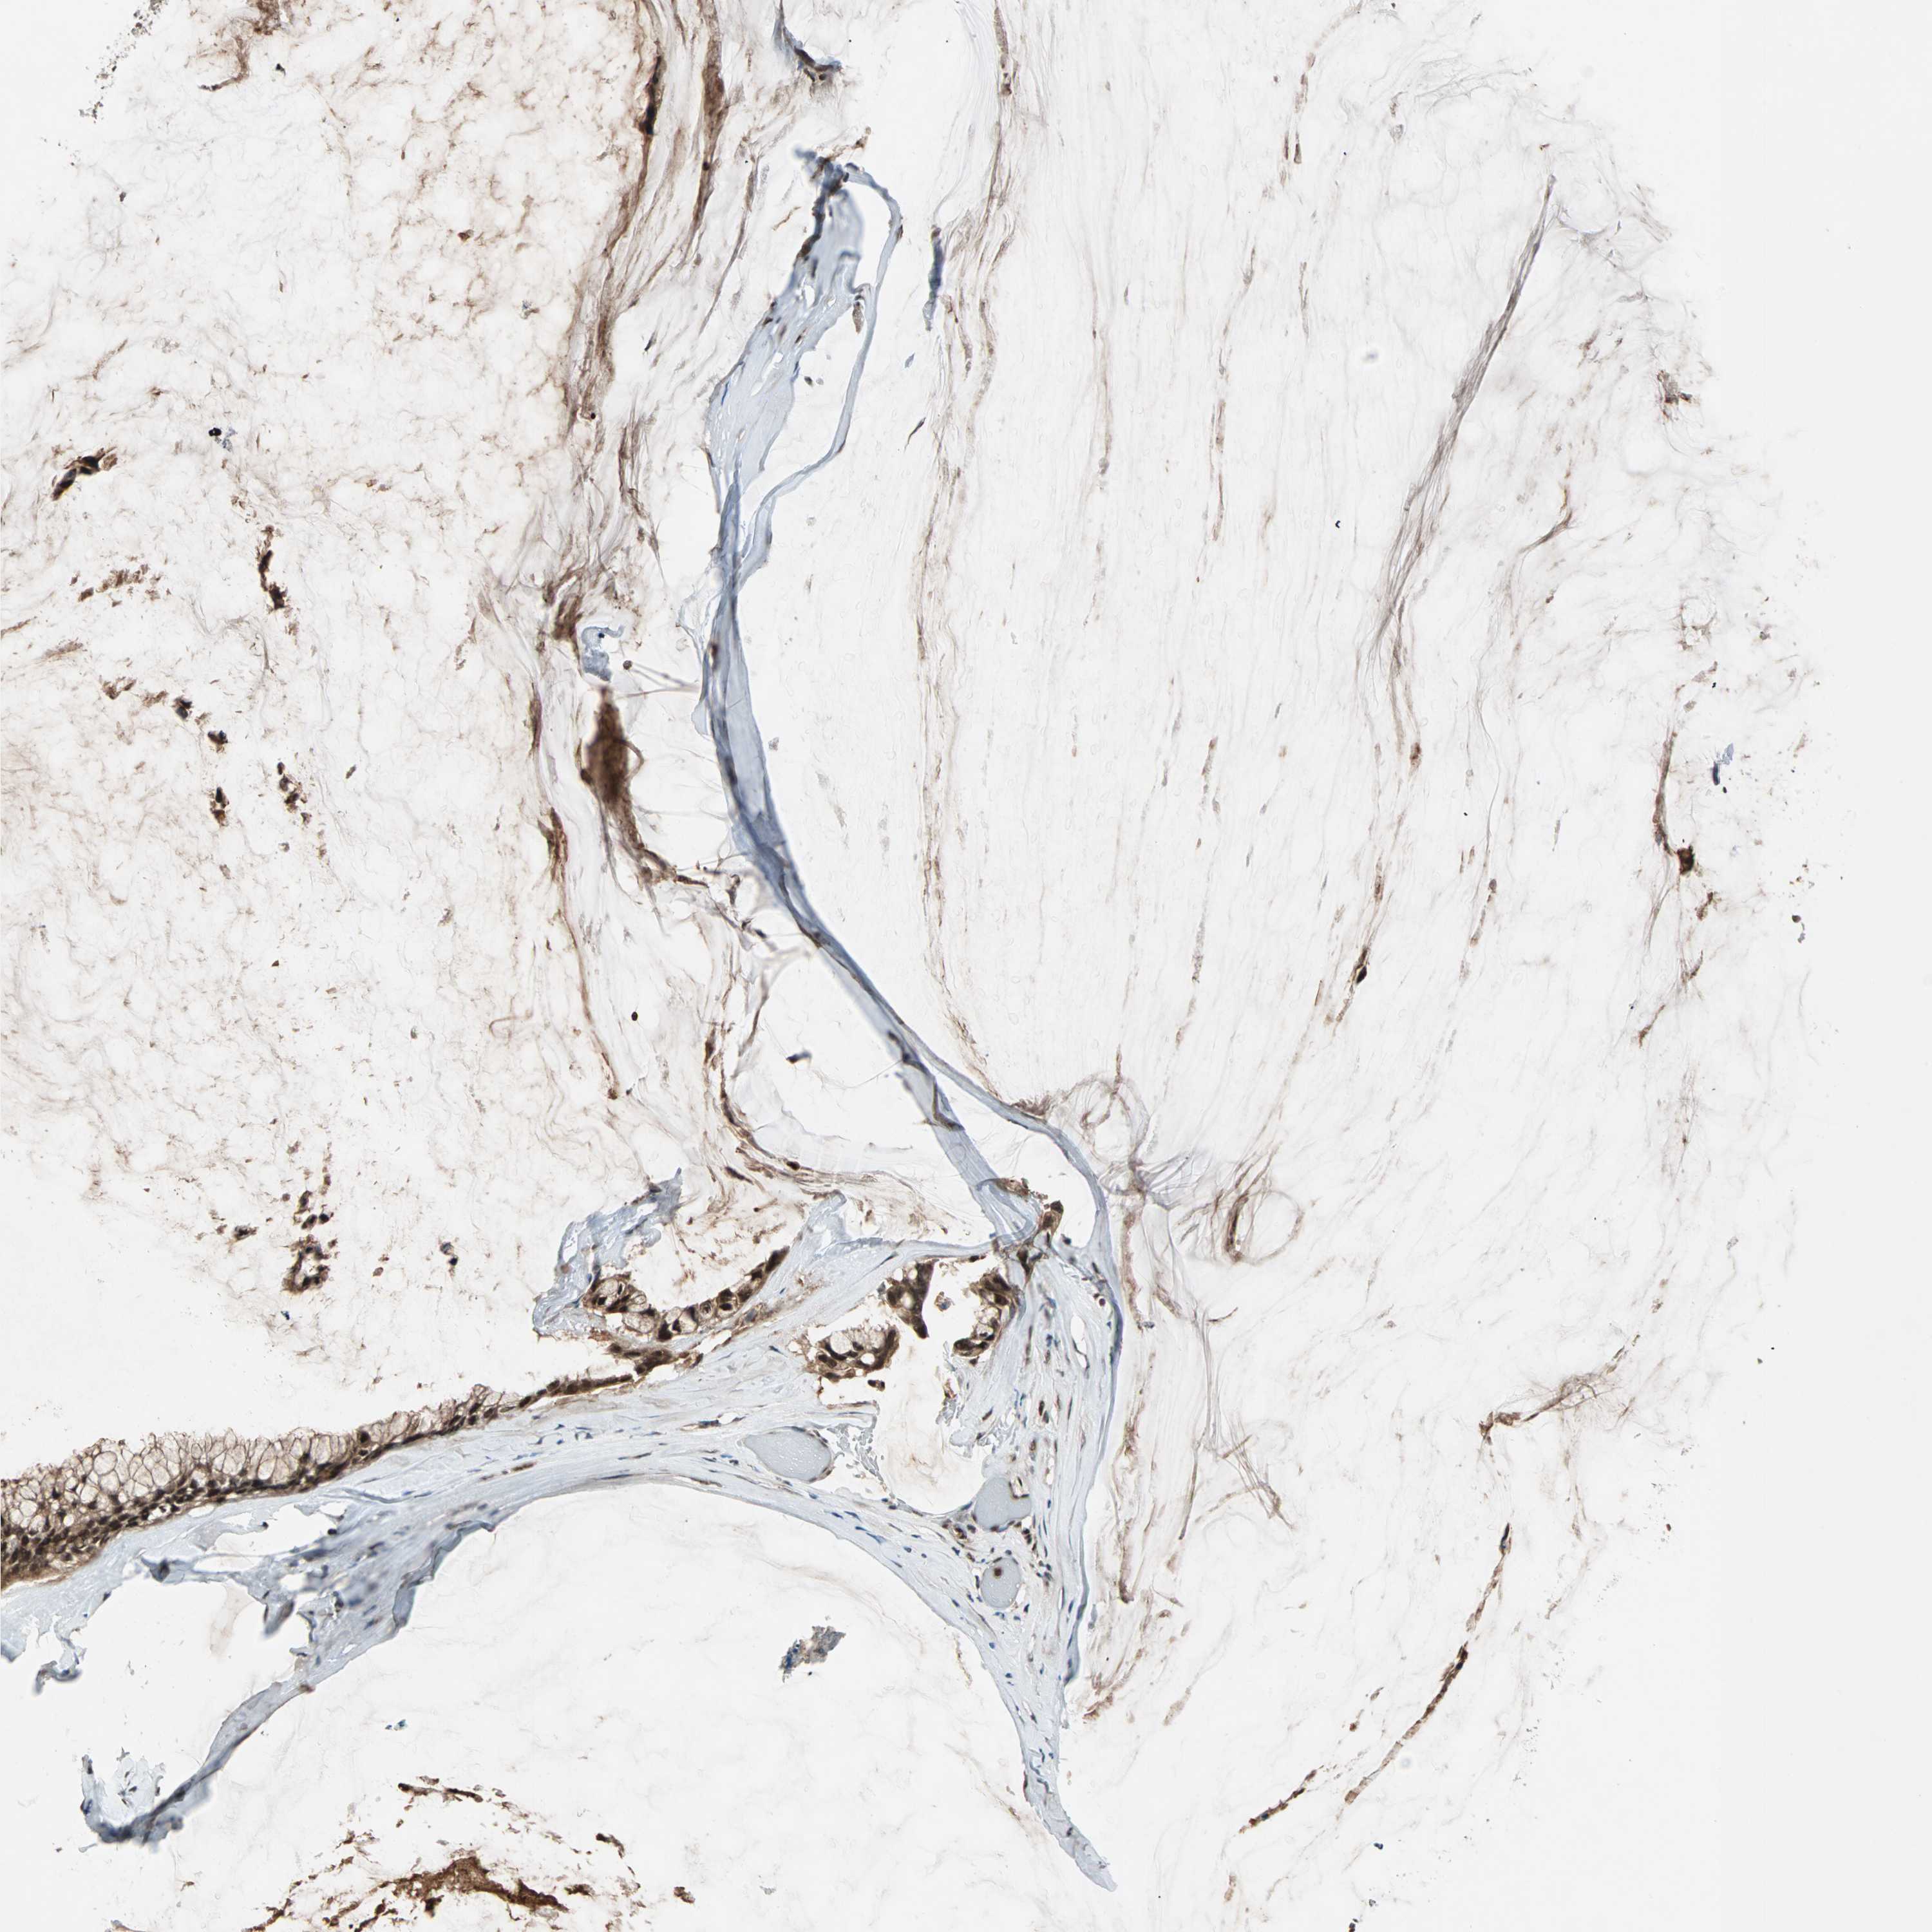

OVARIAN CANCER - Protein expressioni

A mouse-over function shows sample information and annotation data. Click on an image to view it in a full screen mode. Samples can be filtered based on level of antibody staining by selecting one or several of the following categories: high, medium, low and not detected. The assay and annotation is described here.

Note that samples used for immunohistochemistry by the Human Protein Atlas do not correspond to samples in the TCGA dataset.

Antibody stainingi

Antibody staining in the annotated cell types in the current human tissue is reported as not detected, low, medium, or high, based on conventional immunohistochemistry profiling in selected tissues. This score is based on the combination of the staining intensity and fraction of stained cells.

Each image is clickable and will lead to virtual microscopy that enables deeper exploration of all samples and also displays staining intensity scores, fraction scores and subcellular localization as well as patient and tissue information for each sample.

Antibody HPA003146

Staining

High

Medium

Low

Not detected

Intensity

Strong

Moderate

Weak

Negative

Quantity

>75%

75%-25%

<25%

None

Location

Nuclear

Cytoplasmic/membranous

Cytoplasmic/membranous,nuclear

Cystadenocarcinoma, serous, NOS

Carcinoma, endometroid

Carcinoma, NOS

Cystadenocarcinoma, mucinous, NOS